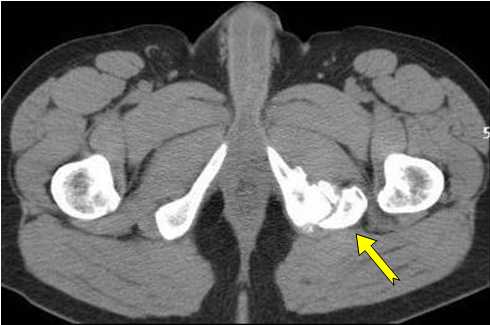

Se le solicitan estudios de laboratorio como hemograma, eritrosedimentación, fosfatasa alcalina, fosfastasa ácida, calcio sérico, fósforo, etc... Los resultados están dentro de los límites normales. Se le realiza una tomografía computerizada: En los cortes axiales se observa una imagen de densidad ósea que se proyecta por debajo y lateralmente al isquion, pero independiente de este, con su centro radiotransparente y sus bordes irregulares (Figura 1). Se observa que la imagen de apariencia tumoral se mantiene separada del isquion (Figura 2).

Figura 1: cortes axiales

Figura 2: Centro de la lesión e imagen tumoral " separada" del isquion.